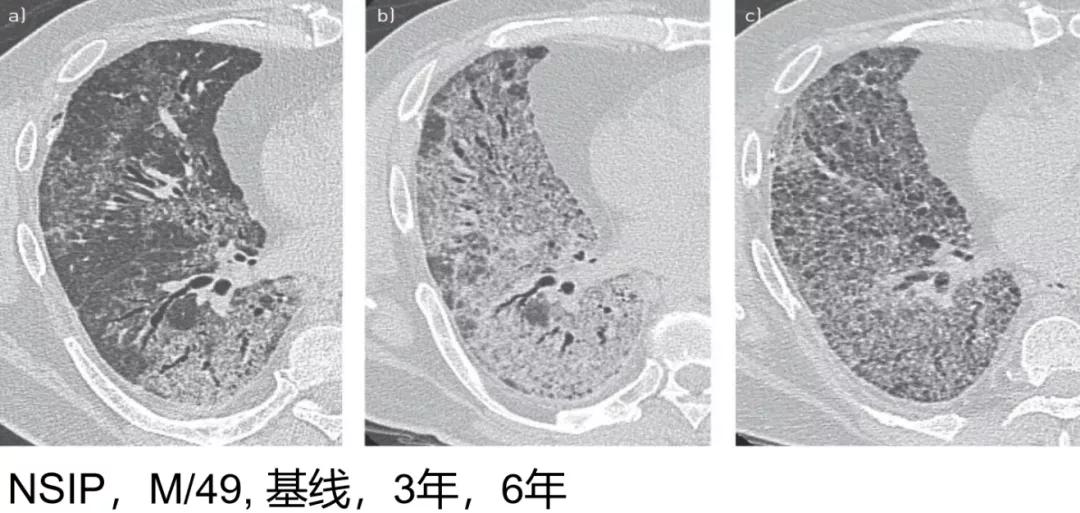

病例1 [22]

这可能是大家在临床中经常见到的一些影像学表现,这是一位49岁的男性PF-ILD,影像最初表现为弥漫的细网格磨玻璃样改变伴牵拉支气管扩张(左),三年后,病变不断扩展,牵拉支气管扩张更加的明显(中)。6年后更加的严重了,肯定是进展的表现了(右)。

(来源:Eur Respir Rev 2018; 27: 180076 [https://doi.org/10.1183/16000617.0076-2018].)